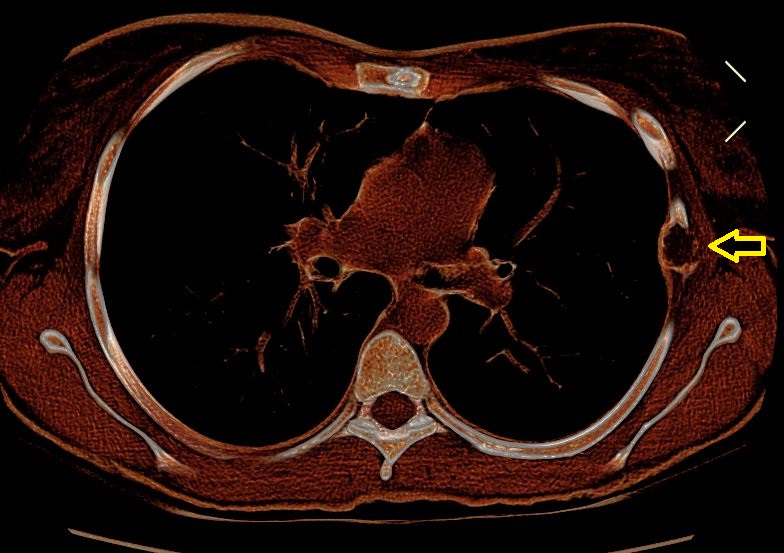

La TAC Torace è fondamentale in questo contesto (Figura 1), anche mediante ricostruzioni 3D (Figura 2)che possono evidenziare la struttura fibrosa dell’osso; la Risonanza Magnetica può aiutare nei casi di diagnosi differenziale.

TAC Torace che mostra una displasia fibrosa a carico della VI costa di sinistra

TAC Torace che mostra una displasia fibrosa a carico della VI costa di sinistra (freccia)